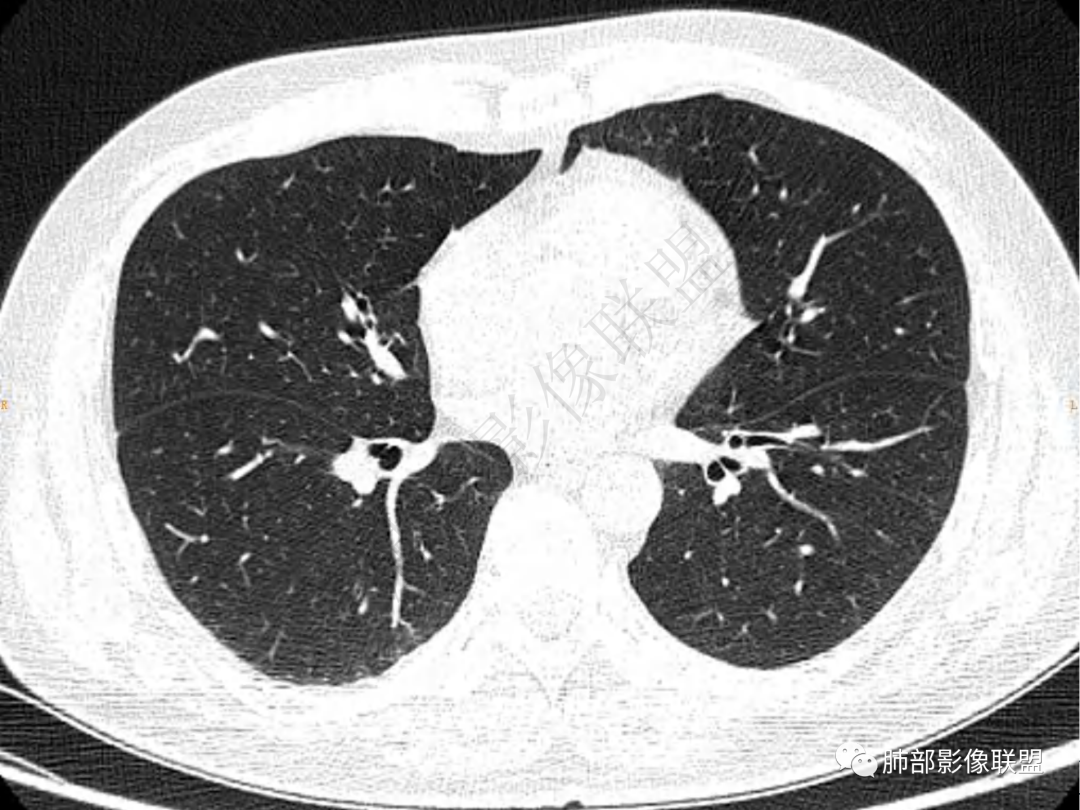

2.左肺下叶团片影,跨背段及内前基底段,实性部分类椭圆形,密度不甚均匀,可见毛刺及棘状突起,未见典型分叶及胸膜凹陷。病灶上下缘可见相应肺段支气管旁进侧出,管壁轻度增厚,未见狭窄阻塞。

3.周边较大范围磨玻璃影,边界相当模糊,小叶增厚明显。注意叶裂另一侧、左肺舌段亦可见磨玻璃影及增厚的小叶间隔。未见明确卫星病灶。

4.实性部分不均匀环形强化并显示一小范围低密度坏死区或空洞。较之肺窗,整体纵隔窗范围较小,提示病灶并不十分密实。抑或为不同时段图像。

5.双肺门及纵隔未见增大淋巴结。未见胸腔积液。